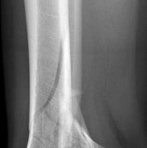

Temporary ankle-spanning external fixation was used to stabilize the fracture and soft tissues. X-rays taken after external fixation showed improved alignment and allowed for better understanding of the fracture pattern (Fig 2.2-2). Computed tomographic (CT) scanning with 3D reconstruction was performed for precise assessment of the fracture pattern of the tibial plafond. The CT revealed displaced fragments with a resultant intraarticular step-off and gap. The distal tibial metaphyseal fracture was multifragmentary. In addition, an associated long oblique fibular fracture was present (Fig 2.2-3).

Fig 2.2-2a–b Realignment of fracture through application of spanning external fixator.

1. AP view.

2. Lateral view.